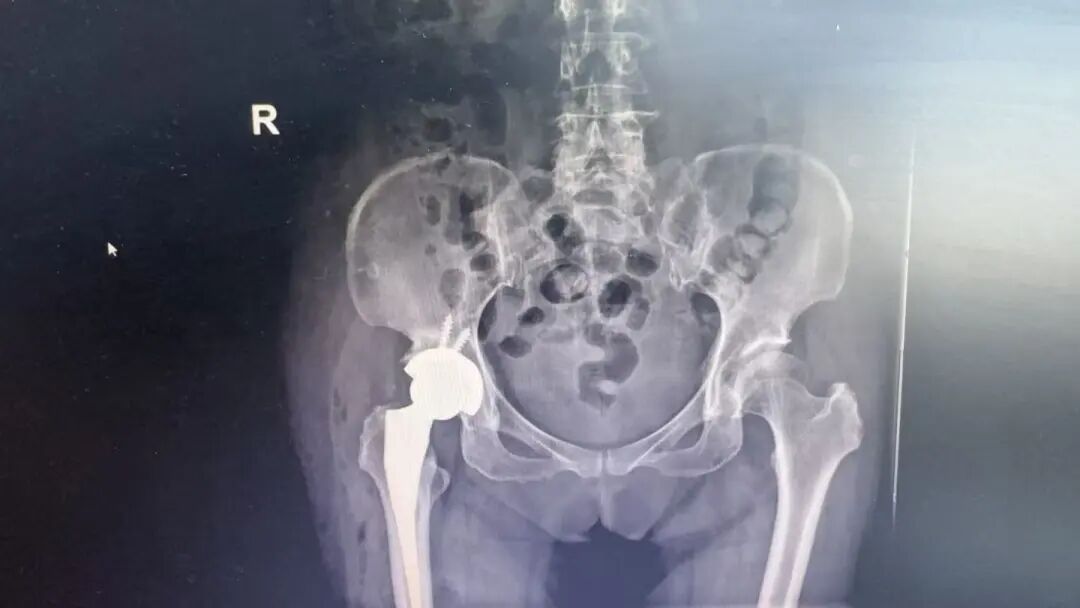

手术当日,张炅教授与凤凰医院骨科团队密切配合,为刘女士实施右侧人工全髋关节置换术。过程顺利,出血量少,假体安放位置精准。术后患者生命体征平稳,安返病房。

在骨科医护人员的精心照护下,刘女士恢复迅速。目前患者关节功能改善显著,疼痛明显缓解,对手术效果非常满意。“真没想到在家门口就能让上海专家做手术,太方便了,为我们老百姓解决了大问题!”刘女士感慨道。